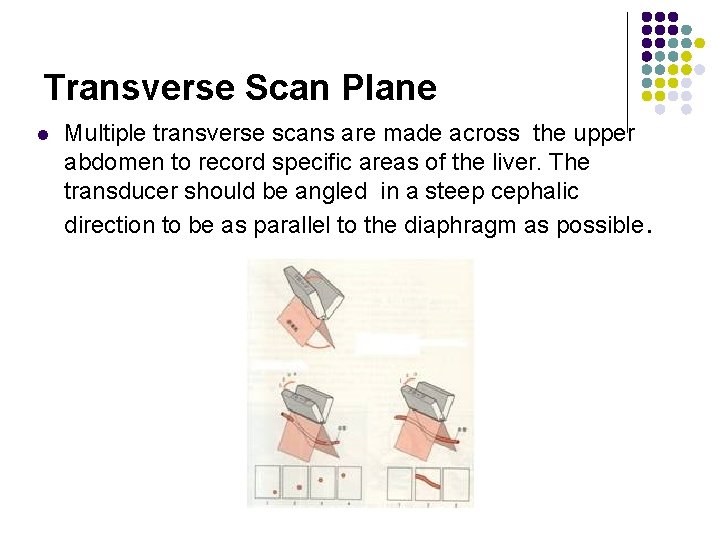

Transverse Scan Plane l Multiple transverse scans are made across the upper abdomen to record specific areas of the liver. The transducer should be angled in a steep cephalic direction to be as parallel to the diaphragm as possible.

l The patient should be in full inspiration to maintain detail of the liver parenchyma , vascular architecture, and ductal structures